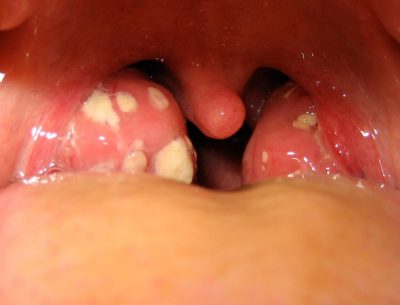

Ağız kokusu ya da yutkunma sırasında sık sık batma şikayetleri yaşayanlarda bademcik taşına sıklıkla rastlıyoruz ...